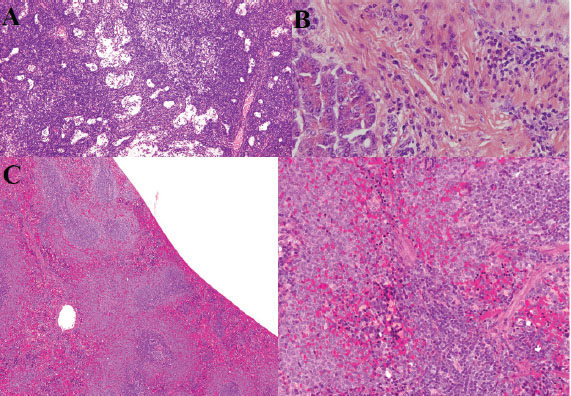

Histopathological findings

Lungs

Severe pulmonary edema, hyaline membrane formation, and intra-alveolar neutrophilic infiltration were noted. Intravascular fibrin thrombi and ectatic alveoli with focal atelectasis were also observed. Occasional megakaryocytes were observed within pulmonary capillaries, along with hemosiderosis and mild anthracosis (Fig. 4A,B). These pulmonary changes are consistent with ALI and DAD.

Heart

The myocardium exhibited moderate lymphoplasmacytic myocarditis with scattered neutrophils, interstitial edema, and cardiomyocyte degeneration. Intravascular neutrophilic accumulation was evident (Fig. 4C,D). The findings suggest that the patient had viral-associated myocarditis.

Liver

Hepatocellular atrophy, sinusoidal dilation, cytoplasmic vacuolation, and scattered necrotic hepatocytes were observed in hepatic sections. Early fibrotic changes were evident, along with mixed mononuclear and neutrophilic infiltration (Fig. 4E,F). The pattern indicates hepatitis with evolving fibrosis, likely related to systemic infection.

Gastrointestinal tract

The gastric submucosa exhibited prominent intravascular neutrophilic aggregates and mononuclear infiltration. Mild mucosal inflammation was also observed (Fig. 4G). These features support the vasculitic involvement of the gastrointestinal tract.

Mesenteric lymph nodes

Histological examination revealed marked architectural disruption with focal eosinophilic necrosis, extensive karyorrhexis, and karyolysis. A notable increase in reactive lymphocytes and plasmacytoid monocytes was observed. Numerous histiocytes were also observed, indicating intense immune activation. The changes reflect severe lymphoid necrosis and immune activation.

Pancreas

The pancreatic tissue showed acute necrotizing inflammation involving both the parenchyma and vascular walls. Focal enzymatic fat necrosis of the peripancreatic adipose tissue was observed, characterized by hemorrhage and ghost-like necrotic adipocytes with granular eosinophilic cytoplasm (Fig. 5A,B). The findings indicate necrotizing pancreatitis with vascular involvement.

Spleen

The spleen exhibited pronounced white pulp atrophy and lymphocyte depletion. Extensive necrosis and vasculitis with arterial thrombosis were observed. Additional findings included congestion, hemorrhage, infarction, acute neutrophilic splenitis, and necrotizing granulomas. Hemophagocytosis was noted along, with the absence of distinct lymphoid follicles (Fig. 5C). These changes are consistent with severe splenic lymphoid depletion and vasculitis.

Fig. 4. Histopathological findings in the lung, heart, liver, and gastrointestinal tract. (A-B) Severe pulmonary edema, hyaline membranes, and vascular thrombosis. (A) Histiocytic, neutrophilic, and lymphoplasmacytic inflammation with multifocal areas of subserosal necrosis with varying degrees. (B) Vascular thrombosis, fibrinoid vasculitis, and syncytial cells. (C–D) Lymphoplasmacytic myocarditis with myocyte degeneration. (C) Hypereosinophilic myocytes and striations. (D) Single apoptotic hepatocyte (600X). (E) Interface hepatitis (piecemeal necrosis), death of hepatocytes at the interface of the parenchyma and connective tissue of the portal zone, accompanied by a variable degree of inflammation and fibrosis. (F–G) Gastric inflammation with neutrophilic vascular aggregates. (F) Jejunum, shortening and loss of epithelial cells with villus fusion and cellular debris along with moderate, multifocal, lympho-plasmacytic-histiocytic inflammation. (G) Ischemia-type colitis showing mucus depletion, patchy atrophic degeneration, polymorphonuclear neutrophil infiltration, and feline coronavirus spike protein in enterocytes and intestinal absorptive cells (Immunohistochemistry, Alkaline Phosphatase (AP), 1000X).

Fig. 5. Histopathology of lymphoid tissues, pancreas, and spleen. (A) Extensive necrosis, vascular thrombosis, cellular debris, lymphoid follicle depletion, and polymorphonuclear neutrophil infiltration. (B) Areas of inflammatory infiltration in the pancreas (hematoxylin and eosin staining, 400X). (C) Depletion of lymphoid follicles in the spleen and reduction of lymphocytes (hematoxylin and eosin staining, 300 dpi).